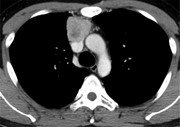

SVC obstruction and stridor relieved by nasogastric tube insertion

Emma J. Molena and others

Journal of Surgical Case Reports, Volume 2016, Issue 3, March 2016, rjw022, https://doi.org/10.1093/jscr/rjw022